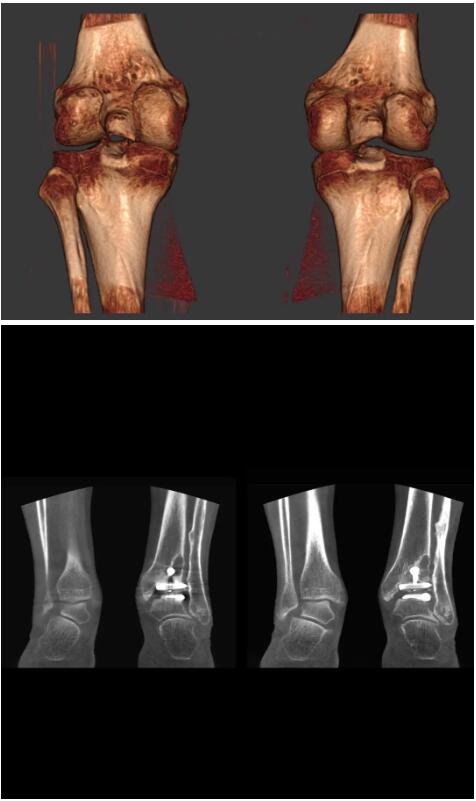

另外一款被稱為世界上最小的CT,它的重量僅300磅,不僅能夠掃查足部,還可以檢查膝蓋和上肢等。

與上面介紹的CT一樣,它同樣具有輻射低、占地空間小(23*36)的特點(diǎn),隨開隨用(支持直接接入墻上的插座)。

這款CT使用非常方便,通過上下移動保持與患者的手臂或者雙腿齊平,掃描快速,僅需要30秒左右就可以完成掃查。

以上介紹的CT均來自國外同一家公司,這些CT均配置了可視化軟件,可以進(jìn)行切片、3D重建以及大型CT附帶的所有典型的操作功能。

以下是這些“特立獨(dú)行”的CT所拍出來的圖像: